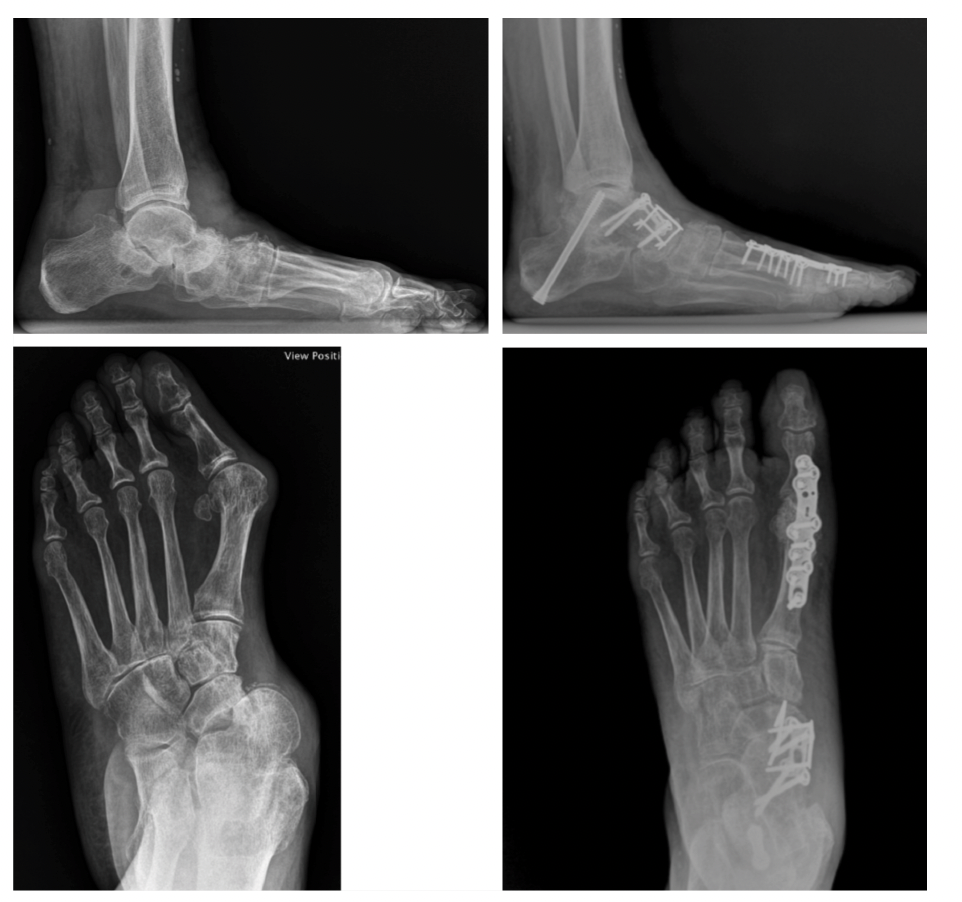

Radiographs are a critical component of the preoperative workup. AP and lateral foot and AP or mortise ankle are mandatory for surgical planning and a hindfoot alignment view is strongly recommended.9 Advances in radiographic imaging leading to the development of weight-bearing CT scanning (WBCT) have led to several paradigm shifts in the understanding of the PCFD deformity and its surgical correction.

The second principle is to correct the rearfoot deformity perpendicular to the ground. When deciding which procedure to perform, the initial distinction is between Evans/medial displacement calcaneal osteotomy (MDCO) or subtalar joint (STJ) fusion. The Evans/MDCO is for moderate, reducible deformities, whereas severe, rigid deformities are best served by STJ fusion. Clinical examination distinguishes between flexible and rigid deformities depending on the degree of reducibility. Severe, advanced deformities necessitating STJ fusion for rearfoot correction demonstrate arthritic changes at the STJ, more significant peritalar subluxation, and more severe collapse of the sagittal height of the foot on plain film radiographs.

With severe deformity with significant peritalar instability, arthrodesis procedures are required for rigid, arthritic, or severe deformities in order to reach the goal of a stable, well-positioned hindfoot.47 For rearfoot correction, the procedure of choice is an STJ fusion. Previous schools of thought have encouraged valgus positioning of the heel during STJ fusion. However, the data actually reveals that the optimal position of the rearfoot is 0–5º of varus on hindfoot alignment view, which equates to a clinically neutral heel.48

The final principle to follow when correcting PCFD is to correct the forefoot parallel to the rearfoot in the coronal plane. Restoration of the medial column is essential for long-term stability of the foot.49 It is often not sufficient to simply correct the rearfoot as there is often a forefoot supinatus element involved, which one can evaluate clinically by loading the foot and comparing the planes of the rear and forefoot.49 The Cotton osteotomy addresses any remaining flexible forefoot supinatus originating from the medial arch. Surgeons can use the Cotton osteotomy with varying graft sizes for deformity-specific correction, but the correction is directly related to the graft size. Research has demonstrated each millimeter of graft to correct the cuneiform articulation angle by 2.1º.50 Graft sizes usually range from 5–11mm.50

A Cotton osteotomy may not always be sufficient. Upwards of 50% of isolated Cotton osteotomies lose correction over time. This loss of correction results from increased motion in the medial column joints.1 If any of the joints of the medial column, including the talonavicular (TNJ), naviculocuneiform (NCJ), or first metatarsal cuneiform joint (first MCJ), exhibit any instability or arthritic changes, they should be fused.49 Considering the loss of correction observed with the Cotton osteotomy and the high prevalence of instability of the first MCJ, the LapiCotton—or Cotton combined with Lapidus—has been popularized to offset these shortcomings. The Lapidus procedure can result in shortening and dorsiflexion of the first ray, but the plantarflexory and grafting components of the LapiCotton provide a powerful combination to reestablish the foot tripod.52 Post-Lapidus, the function of the peroneus longus remains intact; medial column eversion increases at the NCJ if the first ray is not shortened or elevated. The net effect is increased efficiency in stabilizing and locking the first ray.53 This allows realignment of the plantar fascia and facilitates the proper functioning of the windlass mechanism.42